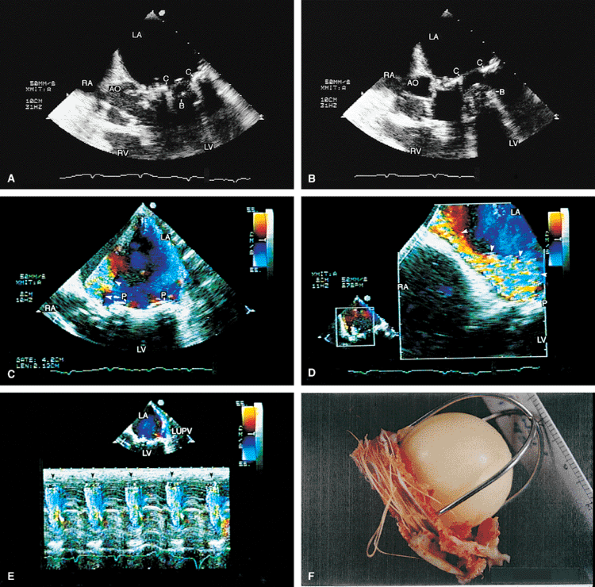

FIGURE 5.13. Mitral annuloplasty ring. A. R demonstrates an annuloplasty ring in the mitral position. S, sutures. B. Color Doppler examination shows aliased inflow signals and prominent diastolic flow acceleration (arrow) produced by narrowing of the mitral orifice by the ring. C. Pulsed-Doppler examination of the left upper pulmonary vein (PV) shows a smaller S wave than D wave, consistent with moderate mitral regurgitation (MR) preoperatively. After ring placement, the S wave is equal to the D wave, suggesting a reduction in mitral regurgitation (in D). E. Another patient in whom the annulus size was reduced to 2.64 cm after placement of an annuloplasty ring for severe MR. LA, left atrium; LV, left ventricle, RV, right ventricle. |

|

FIGURE 5.14. Mitral annuloplasty ring. The ring (R) is seen in diastole in A and in systole in B. C. Color Doppler examination shows moderate residual mitral regurgitation (MR) in this patient, who had severe MR before ring placement. D. A systolic frame shows ring (R) echoes in another patient following mitral annuloplasty. LA, left atrium; LV, left ventricle; MV, mitral valve; PA, pulmonary artery; RV, right ventricle; RVO, right ventricular outflow tract. |